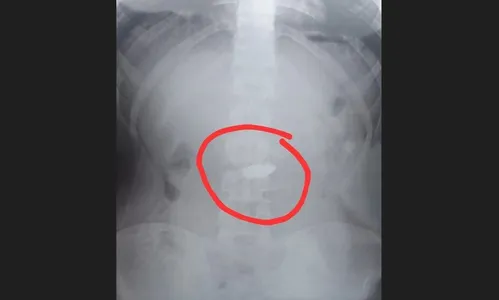

Autor Exame confirmou que rapaz engoliu corrente de ouro - Foto: Reprodução/Prefeitura de Guarujá/Metrópoles

No local, após a realização de um exame de raio X, foi confirmado que a corrente estava no estômago do suspeito. Para resolver a situação, o menor foi submetido a procedimentos para induzir a expulsão do objeto, incluindo o uso de laxantes.